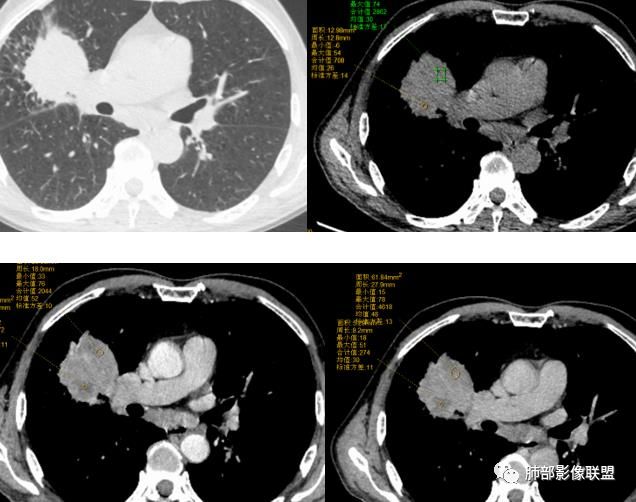

影像表现缺乏特异性,CT最常见的表现是位于周围肺野的实质性肿块,病变部位以上叶多见,常位于胸膜下;

因为病灶有上皮成分和间叶成分,所以兼具肺癌和肺肉瘤的影像学特征,

1.具有肉瘤的特性:肿瘤体积一般较大,直径约大于5cm,边缘清楚、光整,由于肿瘤生长迅速,可见大片坏死,坏死边界清楚;常见支气管推移。

2.具有癌些特性:如分叶、短毛刺、空洞,但是钙化及胸膜凹陷征少见,病灶往往是直接侵犯胸膜,可以远处转移,肺门及纵隔淋巴结可明显肿大;

3.强化方式:增强后病灶以环状强化为主,病灶周边多以癌组织为主,血供丰富,病灶中心区则以肉瘤成分为主,血供较差,易出现粘液样变性、坏死、出血,坏死边界清楚,所以增强CT对PSC与普通型肺癌有一定的鉴别价值。

(中央型PSC肿块常位于肺门处,肿块多较大,边界较光整,伴有阻塞性肺炎或肺不张,与常见类型肺癌不易鉴别。)

病例小结

1.本病例结合病理结果及影像综合分析,应该符合肉瘤样癌,上皮成分是腺癌为主;肿块的边缘毛刺、分叶及周围癌型淋巴管炎征象有符合腺癌的影像表现之处。

2.肿块巨大局部边缘膨隆、光整,坏死较彻底;明显跨叶生长(途经发育不全叶间裂或肺门,注意患者没有胸水),支气管阻塞伴推移等,这些更符合肉瘤的特性。

3.坏死区边界较清楚(皮囊样),环形强化明显,病灶内血管穿行等,都不符合我们常见的鳞癌。

4.肺肉瘤虽然也是肿块巨大,呈大片状坏死,但是边缘光整圆隆,没有分叶、毛刺征象,较少出现肺门及纵隔淋巴结转移。